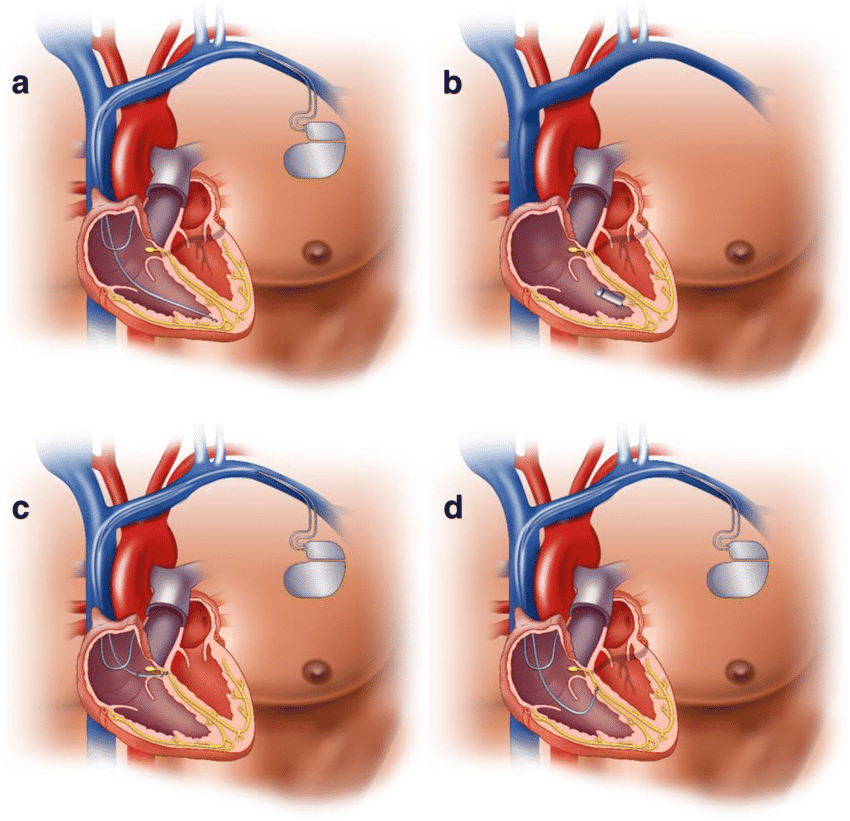

Value added benefits of the Pacemaker Procedure Biventricular:

Value added benefits of the Pacemaker Procedure Double Chamber:

Value added benefits of the ICD:

Value added benefits of the Permanent Pacemaker Implantation:

Value added benefits of the AICD Implantation: